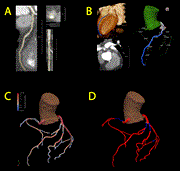

First use of a new extended reality tool for preoperative planning in coronary artery bypass surgery: a case-report

Sulayman el Mathari and others

Journal of Surgical Case Reports, Volume 2024, Issue 6, June 2024, rjae383, https://doi.org/10.1093/jscr/rjae383